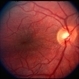

- Multiple retinal folds 4 weeks following vitreous surgery (perfluorodecalin assisted) for retinal detachment with giant retinal tear. OCT shows residual subretinal fluid and outer retinal folds (ORFs) seen as vertical hyperreflective lesions consisting of folded inner segment/outer segment of photoreceptors band and external limiting membrane band.